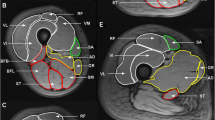

The assumption that a ring-shaped actuator will generate planar waves, which are necessary for 2D MRE (Bishop et al. 2000), has previously been shown to be valid (Klatt et al. 2010), and additionally assumptions of muscle as a linearly viscoelastic, incompressible, locally homogeneous solid (Manduca et al. 2001) were applied. Phase accumulations of greater than ± 2π were corrected using a Laplacian-based phase unwrapping algorithm (Barnhill et al. 2015). The data were then imported to MATLAB, and a custom pipeline (Barnhill et al. 2016) was used to calculate the magnitude of the complex modulus, |G*|. Regions of interest (ROIs) corresponding to the four main quadriceps muscles (i.e. vastus lateralis (VL), rectus femoris (RF), vastus intermedius (VI), vastus medialis (VM)), combined quadriceps muscle, combined hamstrings and adductors and whole thigh (quadriceps, hamstrings and adductors) were manually segmented using ImageJ software (Fig. 3). In areas bordering subcutaneous fat, ROIs were drawn conservatively to reduce the contribution from partial volume effects.

Example anatomy, MRE and fat fraction images from an older and young participant. Cod liver oil capsule denoting the mid-femur point is visible on the anterior surface of the thigh. ROI regions are overlaid on the anatomical image. Quadriceps ROI is represented by black dotted line incorporating RF, VI, VL and VM muscle groups. Whole-thigh ROI includes both quadriceps and hamstrings and adductors ROI. Fat fraction pixel values are scaled from 0 to 50% to aid visualization

The MRI scanning session lasted approximately 30 min and was well tolerated by all participants with no adverse events. Example anatomical, MRE and fat fraction images obtained from a young and older participant are shown in Fig. 3.